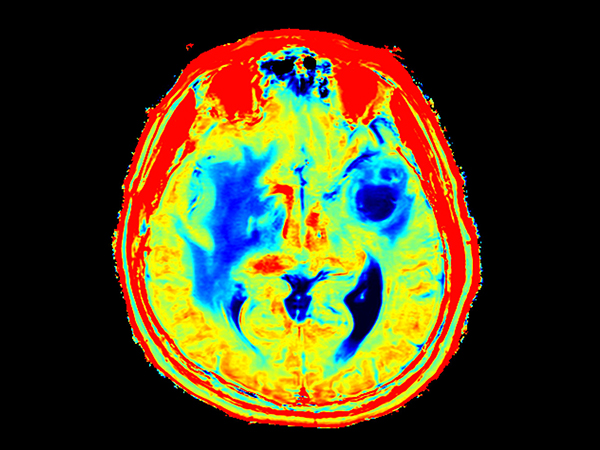

Patient with a large brain lesion. AI based SmartSpeed is utlized to shorten scan time without compromise in image quality. Advanced imaging techniques like pCASL and 3D APT are used to perform contrast-free brain imaging to assess perfusion and tumoral activity. SWIp 3D susceptibility weighted offers the high sensitivity required to visualize deoxygenated (venous) blood or calcium deposits. A single synthetic (SyntAc) brain quantification scan is added. The resulting data of this scan can be used as input for advanced third party processing software* to synthesize MR images with different contrasts, brain parenchyma fraction maps and/or brain segmentation maps.

Axial 3D pCASL (3 dynamics)